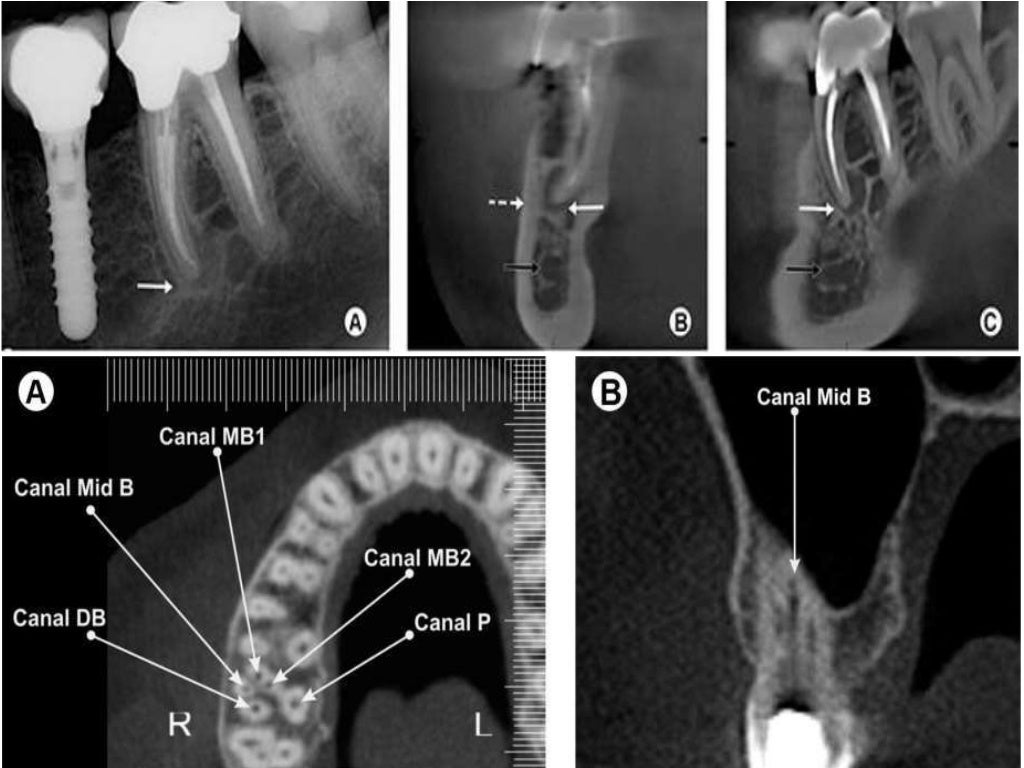

(PDF) Case Report Endodontic Management of Maxillary First Molar Teeth Recent Endodontic Articles We publish research on the health, injuries to, and diseases of the pulp and. An in vitro study gabriela gavilán hadid, miguel. Are they more successful in mature permanent teeth with necrotic pulp than in immature teeth?. The international endodontic journal is a leading international forum for publications in the field of endodontology. Patients with artificial heart valves, past infective. Recent Endodontic Articles.